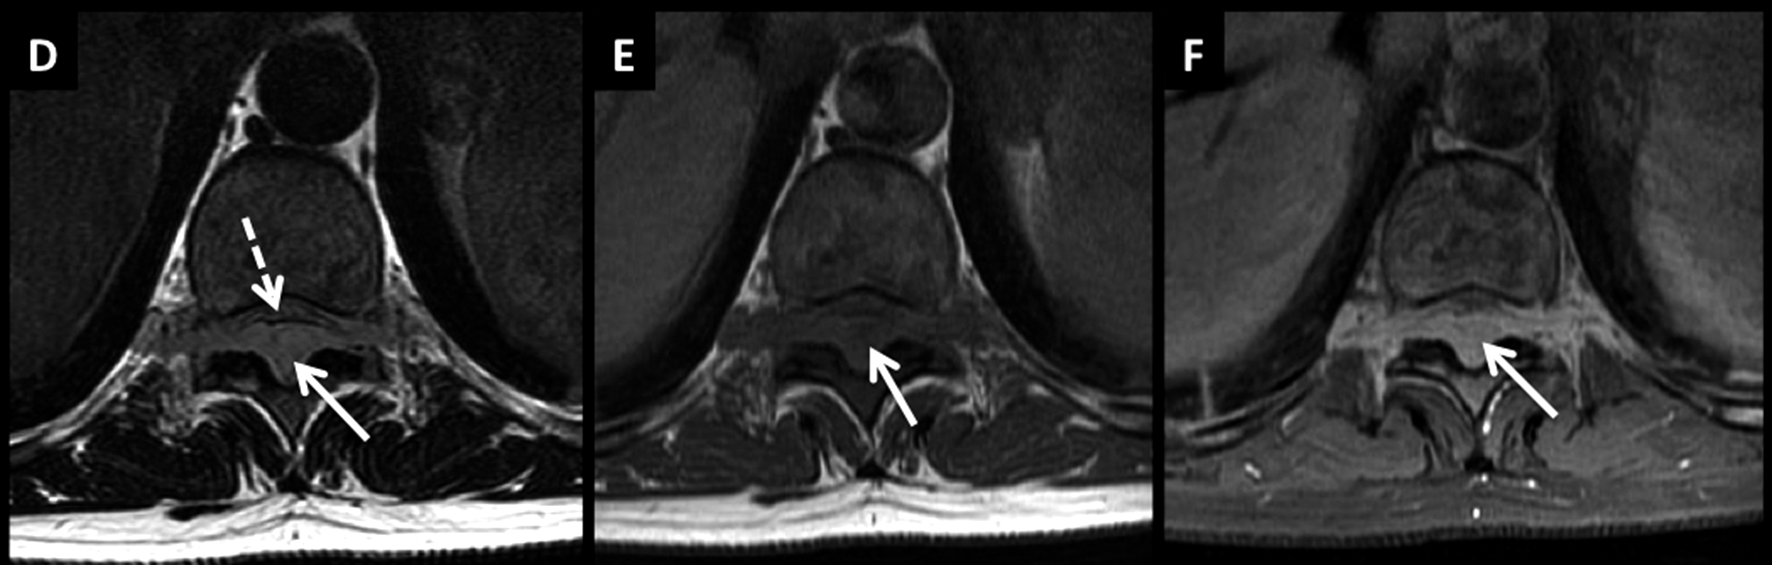

Figura 4

LNH, lesiones óseas y masa extradural, compromiso secundario. (cont)

En el plano axial (D secuencia T2, E secuencia T1 y F secuencia T1 con contraste) se observa la masa descrita con un patrón de crecimiento que lo “amolda” al canal y se extiende a los espacios vecinos a través de los neuro-forámenes del nivel seleccionado.